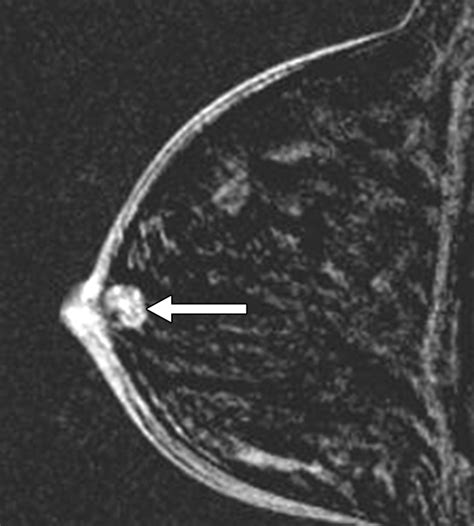

Breast Ultrasound High-resolution imaging used to evaluate lumps and look inside the ducts for abnormal growth.

Ductogram (Galactogram) A specialized test where contrast dye is injected into the affected duct to visualize the blockage or growth.